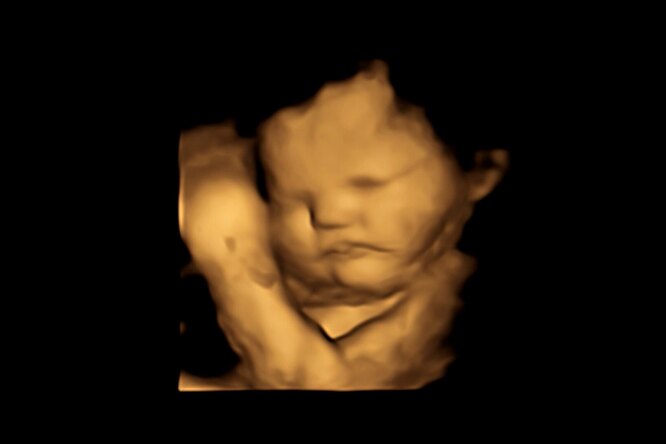

В работе, проведенной Лабораторией исследований плода и новорожденных Даремского университета, Великобритания было проведено 4D-ультразвуковое сканирование 100 беременных женщин, чтобы увидеть, как их нерожденные дети реагировали на воздействие вкусов продуктов, которые ели их матери. (При 4D-ультразвуке генерируется трехмерное движущиеся изображение).

Исследователи наблюдали за тем, как младенцы реагировали на ароматизаторы моркови или капусты вскоре после того, как их получили матери.

У младенцев, получивших порцию моркови чаще было «улыбающееся лицо», в то время как те, кому досталась «капуста», судя по их лицам, были огорчены.

У плода восприятие вкуса и запаха происходит при дыхании или при проглатывании амниотической жидкости в матке.